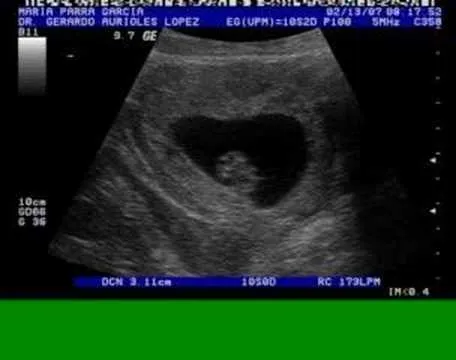

Ultrasonido 9 semanas de embarazo

Este album de Ultrasonido 9 semanas de embarazo con 13 fotos e imágenes no tiene descripción. Puedes sugerir una descripción de éste álbum y publicar nuevas fotos en él.

10 semanas de embarazo ultrasonido - Imagui

Ultrasonido de 9 semanas de embarazo - Imagui

EDSONGCANO: PRUEBA DE EMBARAZO POSITIVA Y ULTRASONIDO NORMAL.